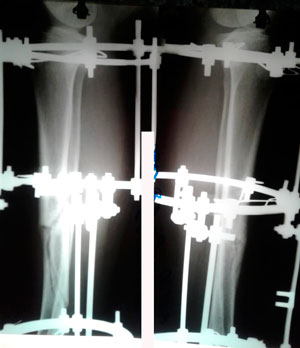

Исходник -43 года.

Дата операции - 18.07.2019г.

Диагноз: нетипичная варусная деформация голеней, на границе нижней и средней/3

Исправление по методике доктора Онипко Н.Н.

Рентген перед фиксацией